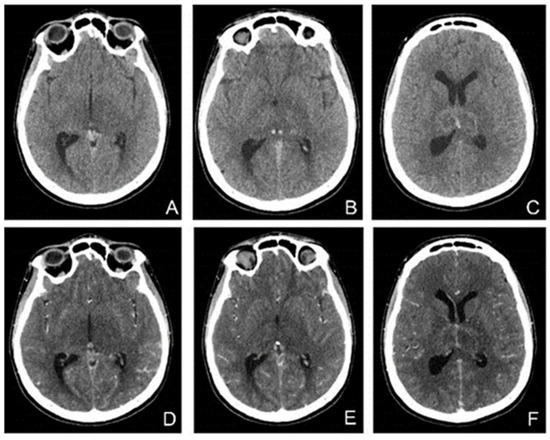

Native head CT performed at admission (Figure 4) showed increased dimensions of sinuses, and hyperdense content in the superior longitudinal sagittal sinus, the right sinus, and, contiguously, the inferior longitudinal sinus as well as in the right transverse sinus and partially the right sigmoid sinus. Additionally, a hyperdense appearance of the cerebellar tentorium raised the suspicion of a subarachnoid hemorrhage. The hypoattenuating brain tissue is suggestive of diffuse cerebral edema.

Figure 4. Unenhanced CT: (A,B)—axial, (C)—coronal, (D)—sagittal exhibits hyperdensity of the venous sinuses (sagittal superior and inferior, right sinus, transverse and sigmoid sinuses). (EH) MRI, (E)—TOF (time of fligt angiography) venous coronal; (F)—T2*hemo axial, (G)—T1 coronal after i.v. contrast, (H)—T1 sagittal after i.v. contrast, expressed extensive thrombosis of all veins.